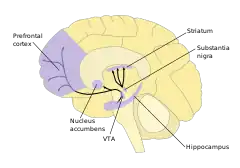

Inside the brain, dopamine plays important roles in executive functions, motor control, motivation, arousal, reinforcement, and reward, as well as lower-level functions including lactation, sexual gratification, and nausea. The dopaminergic cell groups and pathways make up the dopamine system which is neuromodulatory.

Dopaminergic neurons (dopamine-producing nerve cells) are comparatively few in number—a total of around 400,000 in the human brain[41]—and their cell bodies are confined in groups to a few relatively small brain areas.[42] However their axons project to many other brain areas, and they exert powerful effects on their targets.[42] These dopaminergic cell groups were first mapped in 1964 by Annica Dahlström and Kjell Fuxe, who assigned them labels starting with the letter "A" (for "aminergic").[43] In their scheme, areas A1 through A7 contain the neurotransmitter norepinephrine, whereas A8 through A14 contain dopamine. The dopaminergic areas they identified are the substantia nigra (groups 8 and 9); the ventral tegmental area (group 10); the posterior hypothalamus (group 11); the arcuate nucleus (group 12); the zona incerta (group 13) and the periventricular nucleus (group 14).[43]

The substantia nigra is a small midbrain area that forms a component of the basal ganglia. This has two parts—an input area called the pars compacta and an output area the pars reticulata. The dopaminergic neurons are found mainly in the pars compacta (cell group A8) and nearby (group A9).[42] In humans, the projection of dopaminergic neurons from the substantia nigra pars compacta to the dorsal striatum, termed the nigrostriatal pathway, plays a significant role in the control of motor function and in learning new motor skills.[44] These neurons are especially vulnerable to damage, and when a large number of them die, the result is a parkinsonian syndrome.[45]

The ventral tegmental area (VTA) is another midbrain area. The most prominent group of VTA dopaminergic neurons projects to the prefrontal cortex via the mesocortical pathway and another smaller group projects to the nucleus accumbens via the mesolimbic pathway. Together, these two pathways are collectively termed the mesocorticolimbic projection.[42][44] The VTA also sends dopaminergic projections to the amygdala, cingulate gyrus, hippocampus, and olfactory bulb.[42][44] Mesocorticolimbic neurons play a central role in reward and other aspects of motivation.[44] Accumulating literature shows that dopamine also plays a crucial role in aversive learning through its effects on a number of brain regions.[46][47][48]

Basal ganglia

The largest and most important sources of dopamine in the vertebrate brain are the substantia nigra and ventral tegmental area.[42] Both structures are components of the midbrain, closely related to each other and functionally similar in many respects.[42] The largest component of the basal ganglia is the striatum.[52] The substantia nigra sends a dopaminergic projection to the dorsal striatum, while the ventral tegmental area sends a similar type of dopaminergic projection to the ventral striatum.[42]